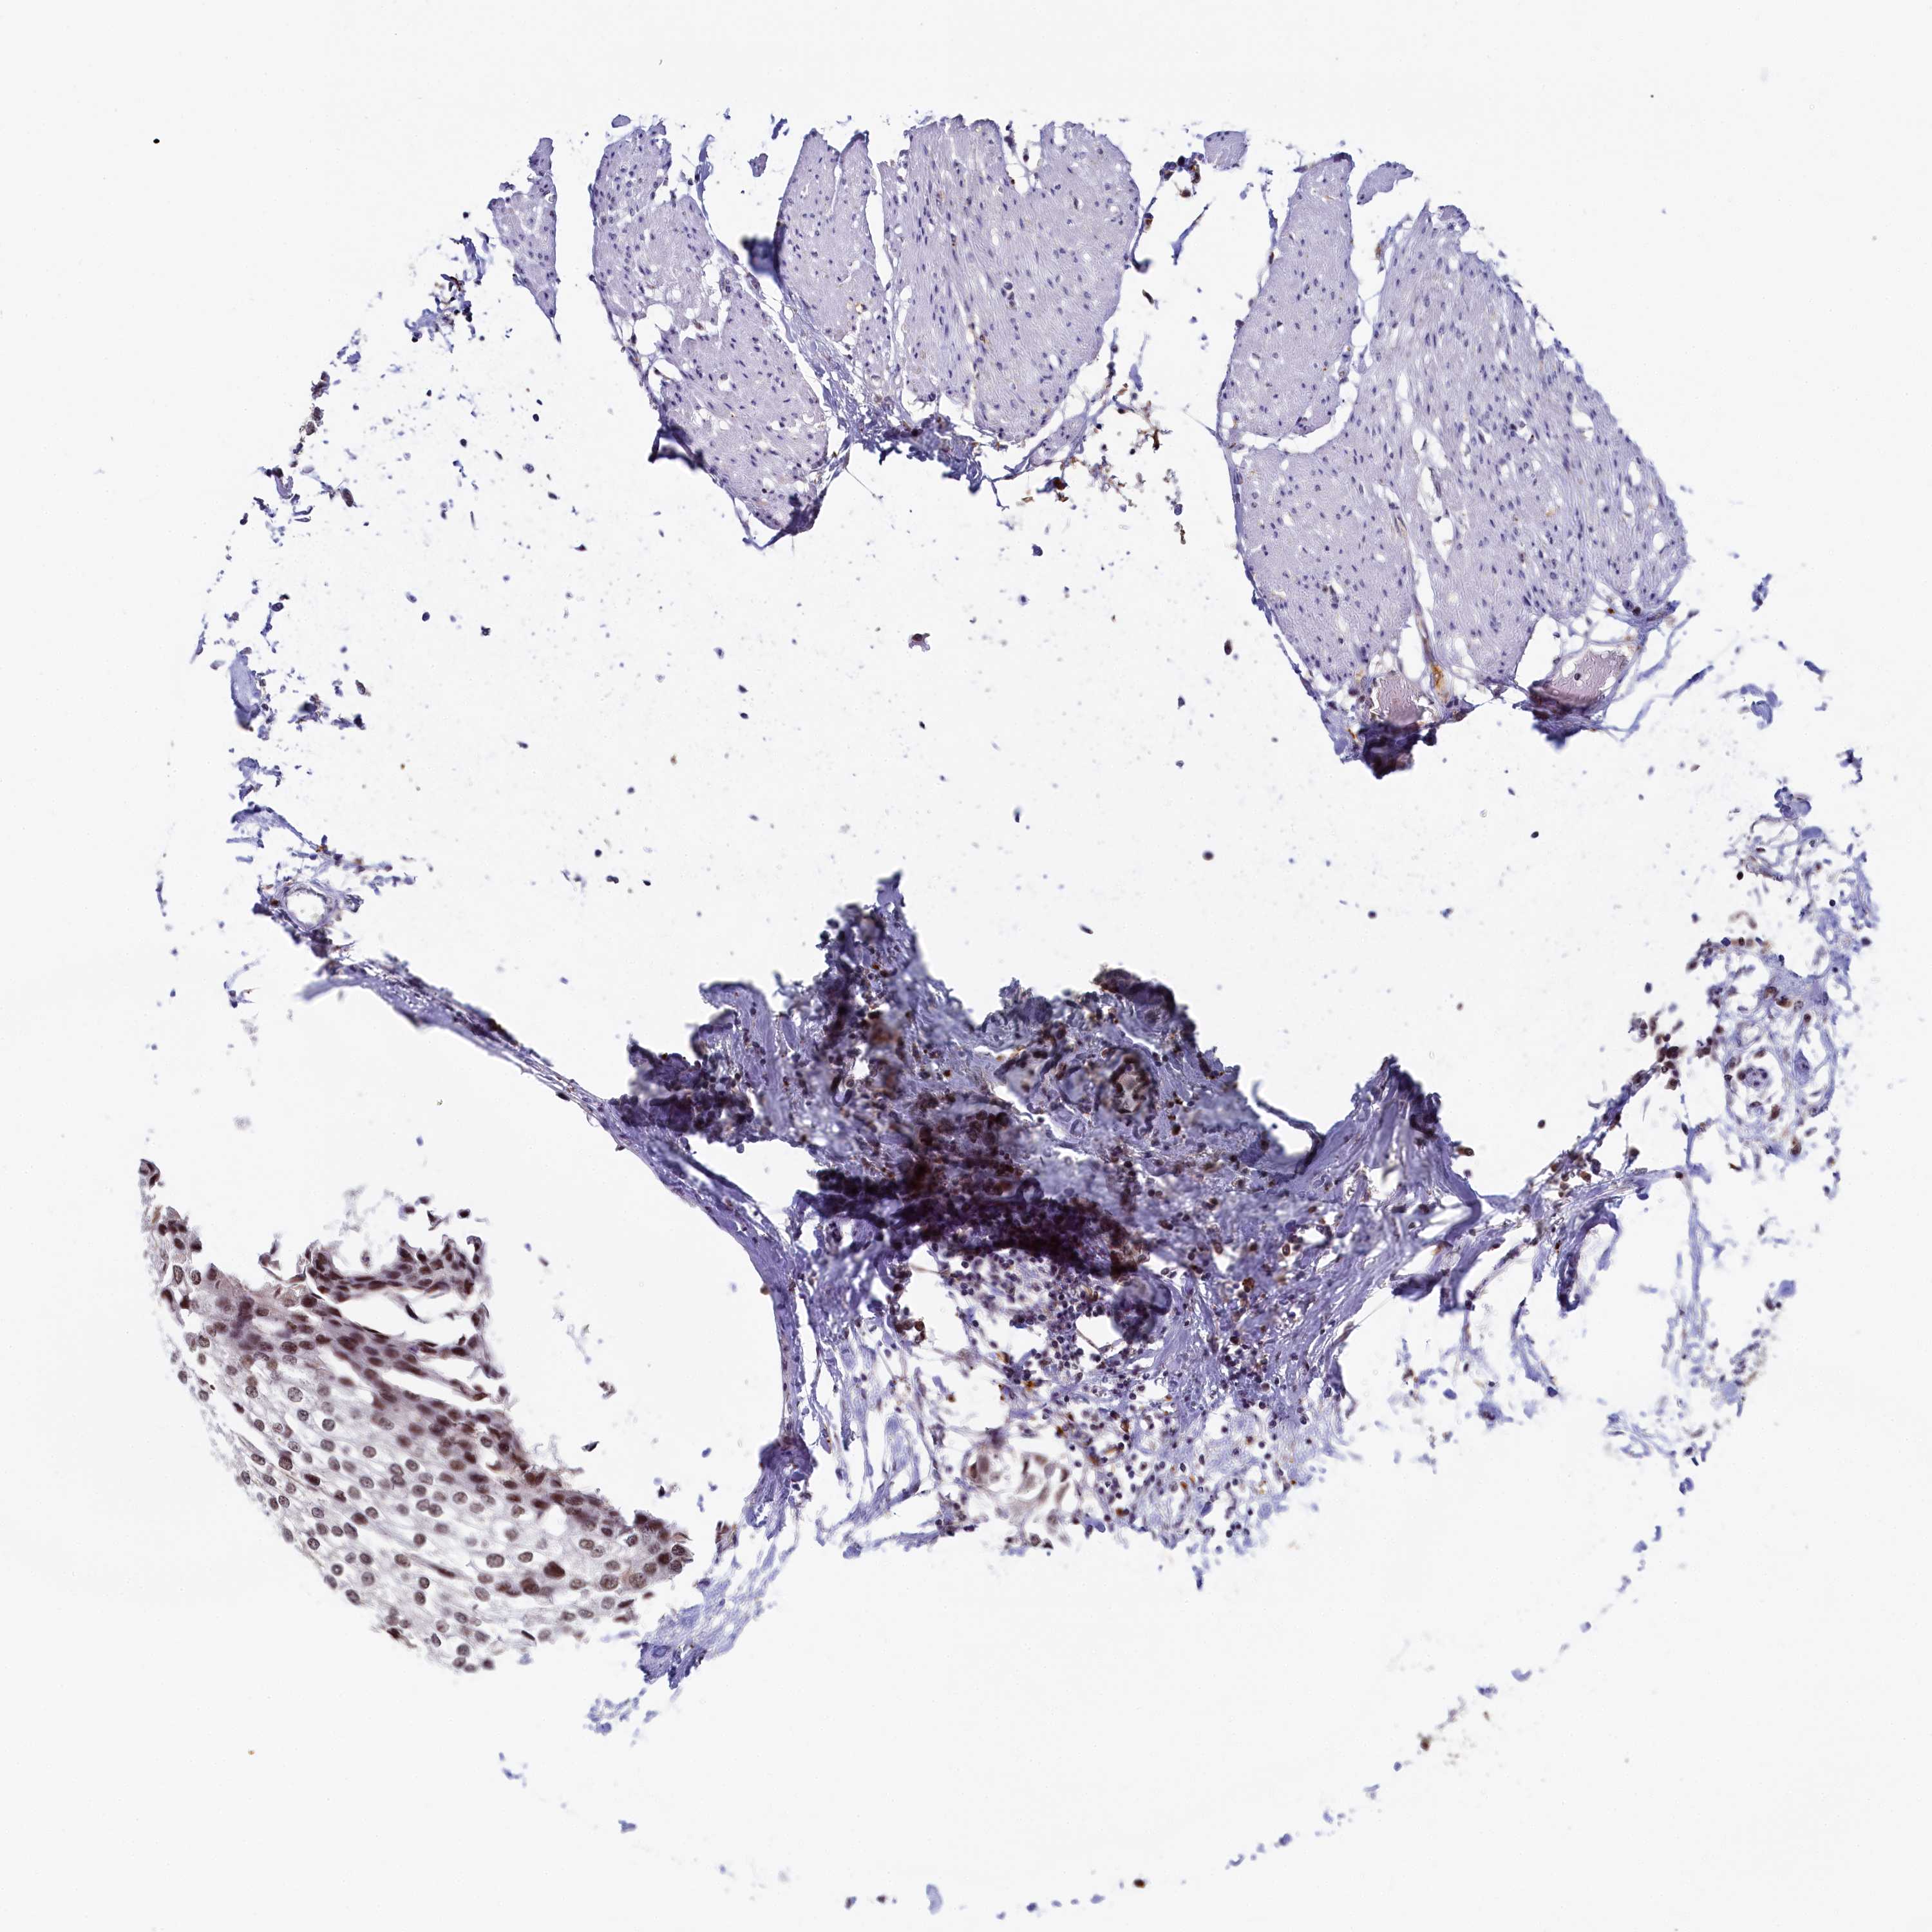

UROTHELIAL CANCER - Protein expressioni

A mouse-over function shows sample information and annotation data. Click on an image to view it in a full screen mode. Samples can be filtered based on level of antibody staining by selecting one or several of the following categories: high, medium, low and not detected. The assay and annotation is described here.

Note that samples used for immunohistochemistry by the Human Protein Atlas do not correspond to samples in the TCGA dataset.

Antibody stainingi

Antibody staining in the annotated cell types in the current human tissue is reported as not detected, low, medium, or high, based on conventional immunohistochemistry profiling in selected tissues. This score is based on the combination of the staining intensity and fraction of stained cells.

Each image is clickable and will lead to virtual microscopy that enables deeper exploration of all samples and also displays staining intensity scores, fraction scores and subcellular localization as well as patient and tissue information for each sample.

Antibody HPA040255

Antibody HPA040651

Urothelial carcinoma, High grade

Urothelial carcinoma, Low grade